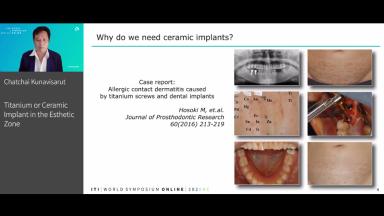

Although titanium has been the gold standard as “the implant material of choice” for decades, recently there has been increasing demand for non-metal implant materials. Some practitioners recommend the zirconia implant in the esthetic zone claiming various advantages including a reduction in the grayish color from metal shining through the soft tissues, biocompatibility and a good soft tissue response. However, there are only a few studies on the short-term success of zirconia implants. Patient selection also plays an important role in esthetic success. This lecture will present the case selection procedure for the choice between titanium and zirconia implants in the esthetic zone. Surgical and prosthetic techniques will be discussed and the preliminary results of 3.3 zirconia implants placed in the Asian population will also be presented.